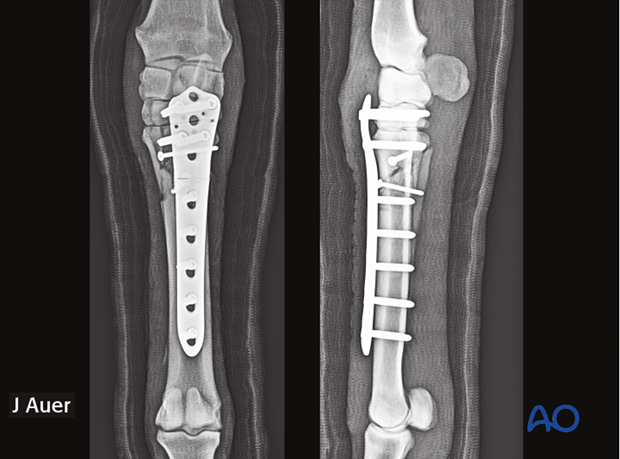

The fracture is anatomically reduced and repaired with one or two plates spanning the entire bone and applied at 90° relative to each other (left). In small ponies, some foals and selective cases of adult horses only one plate may be selected (right).

Occasionally even an adjacent row of bones may be used to achieve additional purchase. The distal row of carpal/tarsal bones lend themselves for this techniques because they form non-moving joints with the proximal McIII/MtIII respectively.

In selected cases of proximal metaphyseal fractures, the distal row of carpal/tarsal bones can be included in the fixation because these joints do, for practical purposes, not move. This allows the insertion of additional screws into the distal row of carpal/tarsal bones associated with a functional arthrodesis of the carpometacarpal/tarsometatarsal joint.

Because of the additional purchase of screws it may be possible to only use one (special) plate for the fixation in association with full limb external coaptation for a prolonged period of time.